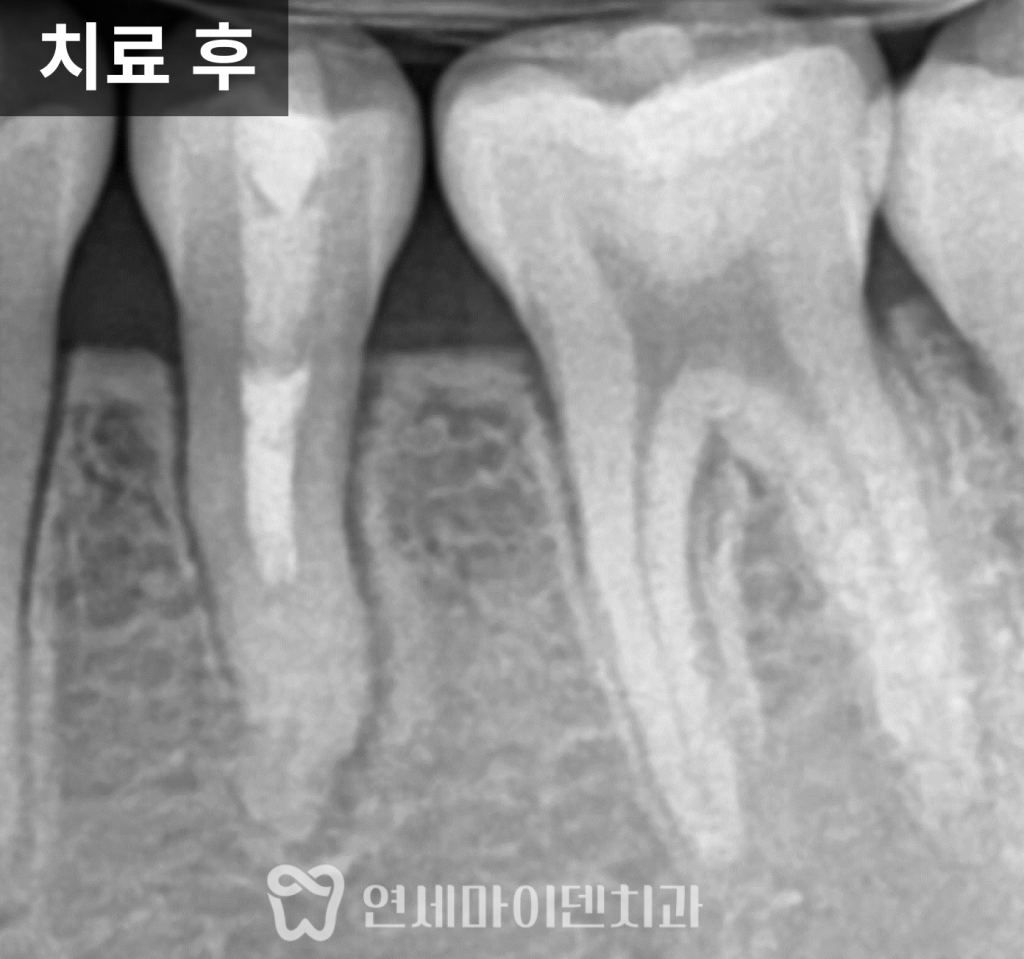

그래서 이번 케이스에서는

치근단 형성술을 선택했습니다.

이 치료는 뿌리 끝의 살아있는 조직을 최대한 보존해

시간이 지나면서 뿌리 길이와 두께가

자연스럽게 성장하도록 유도하는 방법입니다.

치료 과정과 보존적 마무리

치아 내부 감염을 제거하기 위해

신경치료를 진행했지만,

뿌리 끝까지 완전히 밀폐하는 방식이 아니라

성장을 고려해 중간 단계까지 치료를 진행했습니다.

또한 아직 성장기라는 점을 고려해

크라운과 같은 보철 치료는 진행하지 않고,

레진으로 외형을 보존하는

보존적인 방식으로 마무리했습니다.

이렇게 하면

치아 삭제를 최소화하면서

성장 가능성을 유지할 수 있습니다.